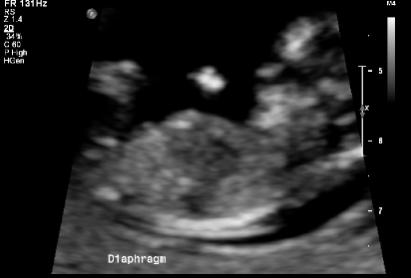

Are there any guesses???Attachment 20803Attachment 20804